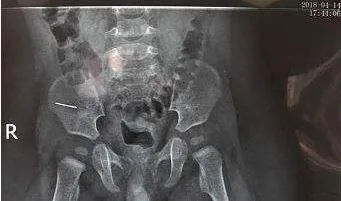

男婴经过治疗后,在10月26日的时候出院了。但在10月31日的时候,男婴再次被紧急送到了医院,医生发现,男婴颅脑多处骨折,肋骨骨折!这名50天的男婴因病情严重,被立马转入了儿科重症监护病房!